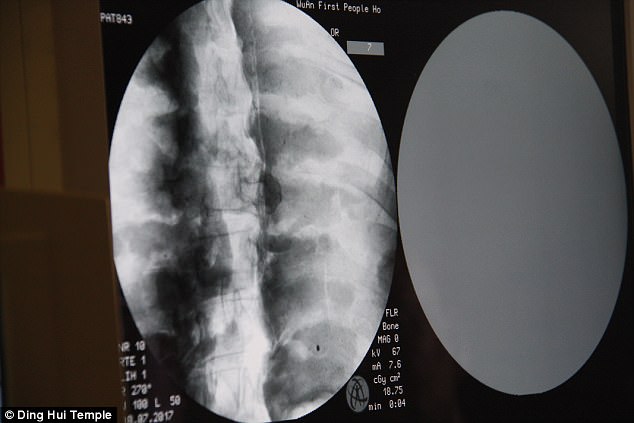

Sự kiện gây chấn động diễn ra vào ngày 8 tháng 7 năm 2017, khi các nhà khoa học tiến hành chụp CT để kiểm tra bên trong "bức tượng" này trước sự chứng kiến của giới truyền thông và đông đảo người dân. Kết quả hình ảnh quét được đã khiến tất cả những người có mặt phải bàng hoàng. Các bác sĩ xác nhận rằng bên dưới lớp mạ vàng, nhà sư Ci Xian vẫn giữ được bộ xương nguyên vẹn cùng một bộ não hoàn chỉnh.

Bác sĩ Wu Yongqing, người trực tiếp tham gia buổi kiểm tra cho biết xương của ngài khỏe mạnh và rõ ràng như một người bình thường. Từ xương hàm trên, răng, xương sườn, xương sống cho đến tất cả các khớp đều vẫn còn nguyên vẹn một cách khó tin. Sự tồn tại hoàn hảo của thi hài sau hơn 1.000 năm đã chứng minh kỹ thuật ướp xác đỉnh cao thời bấy giờ, tạo nên một hiện tượng chấn động khiến cả thế giới phải chú ý.

Những hình ảnh có được sau khi chụp CT